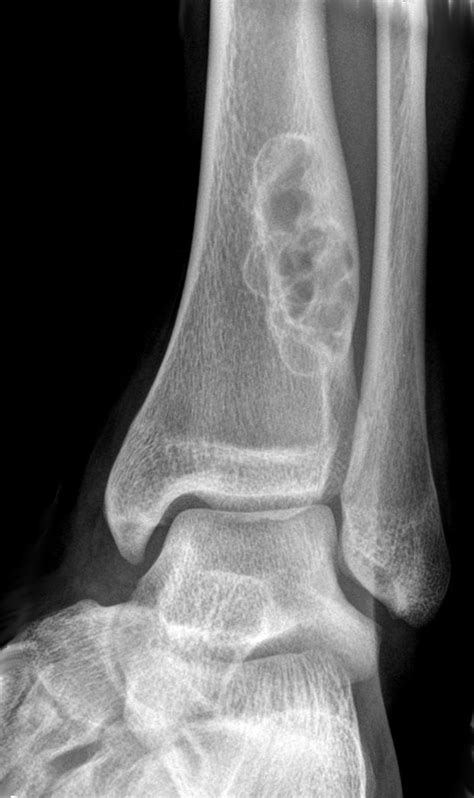

• Location: Primarily found in the long bones of the legs, such as the femur (thigh bone) or the tibia (shin bone).

• Appearance: On an X-ray, they appear as a well-defined, multi-lobulated or "bubbly" lucency within the cortex of the bone.

• Margins: They usually have a thin, sclerotic rim of bone, which indicates that the lesion is stable and not actively aggressive.